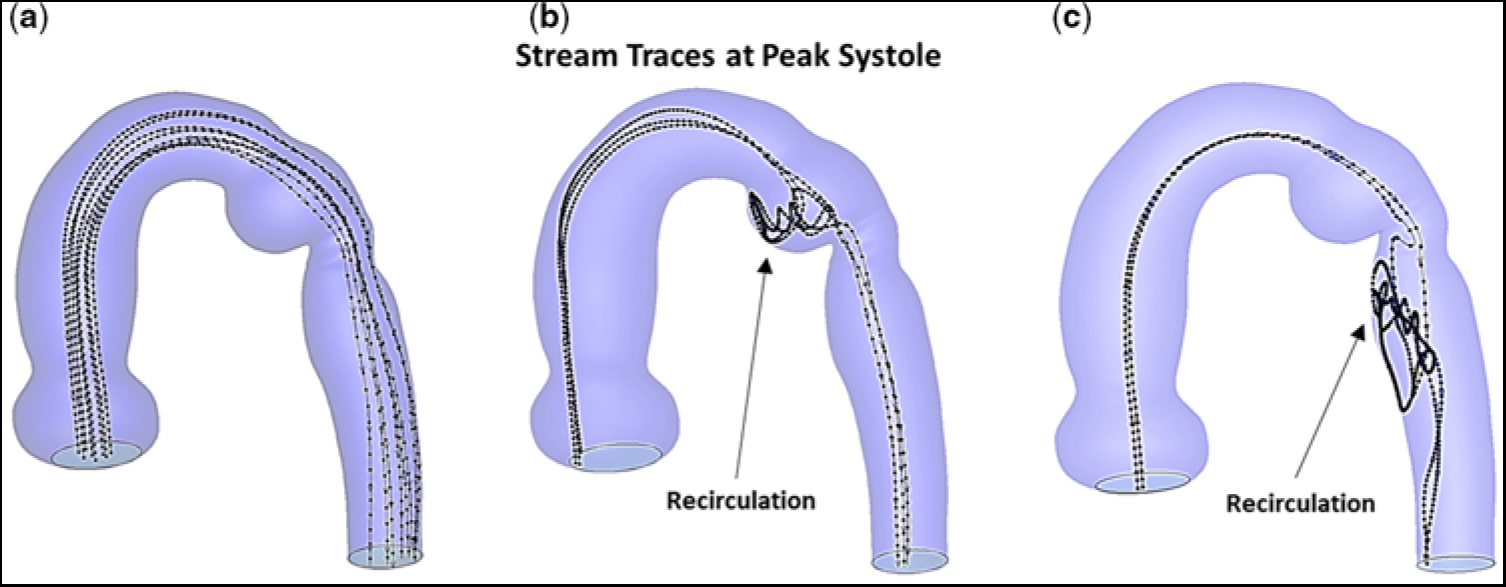

In actuality, blood is composed of plasma and formed elements, which are made-up of blood cells and platelets. Typically, the red blood cells concentrate near, and flow along, the central axis of an arterial vessel. However, due to a balance between viscous drag and inertial forces,Reference Segre and Silberberg20, Reference Segre and Silberberg21 the much smaller platelets tend to reside away from the central axis, and flow closer to the vessel wall, i.e., outward typically at ∼60% of the vessel radius.Reference Segre and Silberberg20–Reference Mountrakis, Lorenz and Hoekstra22 This led us to compare stream traces, at peak systole, and prior to stent implantation, for hypothetical particles released near the central axis to those for particles initially positioned outward from the central axis at ∼60% of the vessel radius. Figure 6 shows the corresponding stream traces for particles flowing throughout the aortic arch with re-coractation. Each stream trace remained unperturbed in the ascending aorta and transverse aortic arch, since there was no obstruction. Importantly, particles positioned near the central axis readily bypassed the ampulla and flowed undisturbed through the descending aorta, Figure 6a. In contrast, particles released at ∼60% of the vessel radius, Figure 6b and c, become entrapped in the ampulla (Fig 6b) prior to entering the descending aorta, or in a region on the medial aspect of the descending aorta just beyond the isthmus (Fig 6c). These are zones containing low-velocity re-circulating flow. Thus, particles in these areas would experience an increased residence time; and, therefore, if they were platelets, would be more likely to undergo activation/aggregation.

Figure 6. Stream traces, at peak systole, and prior to stent implantation. (a) Hypothetical particles released near the central axis. (b) Particles released lateral to the central axis and positioned at ∼60% of the vessel radius. (c) Particles released posterior to the central axis and positioned at ∼60% of the vessel radius. Note, in (b) and (c), particles released away from the central axis become trapped in the ampulla and undergo recirculation or become trapped in an elongated zone in the descending aorta and undergo recirculation.